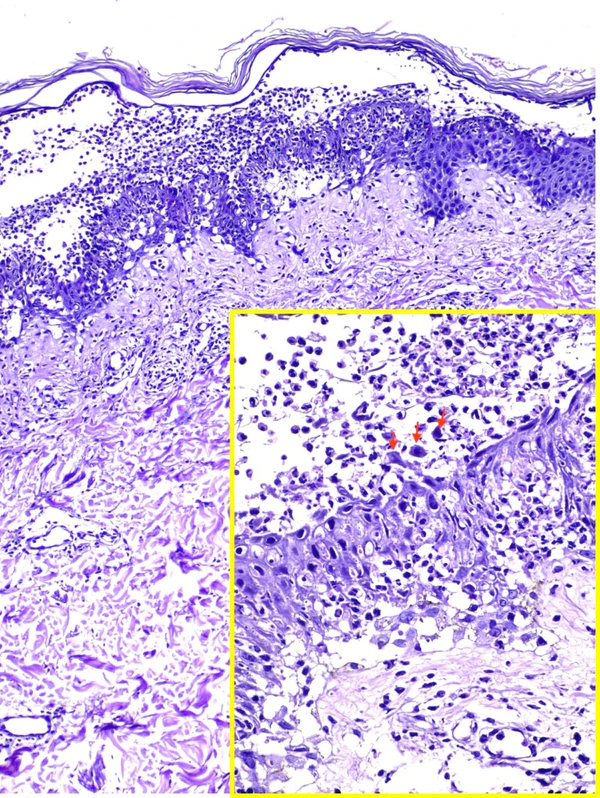

Гистологическое исследование образцов кожи выявляет внутриэпидермальные пустулы с нейтрофильной инфильтрацией, минимальным акантолизом и межклеточными отложениями IgA в эпидермисе. При подтипе субкорнеального пустулёзного дерматоза изменения локализуются преимущественно субкорнеально (в верхних слоях эпидермиса), при внутриэпидермальном нейтрофильном дерматозе — в нижних и средних слоях эпидермиса[2][5].